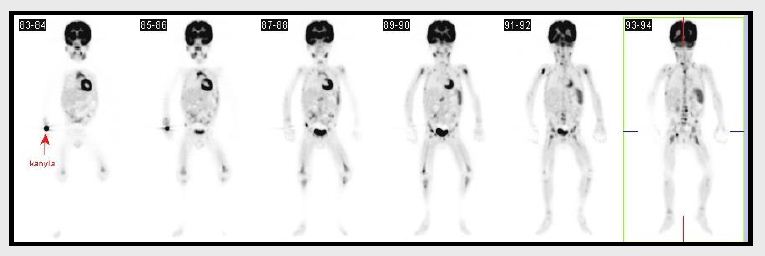

1. pacient

Dvouletý chlapec vyšetřen na PET/CT pro horečky

nejasného původu. Na PETu nalezena ložiska v kalvě vpravo

frontálně, dlouhých kostech (hlavice obou humerů, hlavice femuru a

dolní konec pravého femuru), patologicky kumulující ložiska v

páteři L3 a Th7 a četné nálezy v pánevních kostech.